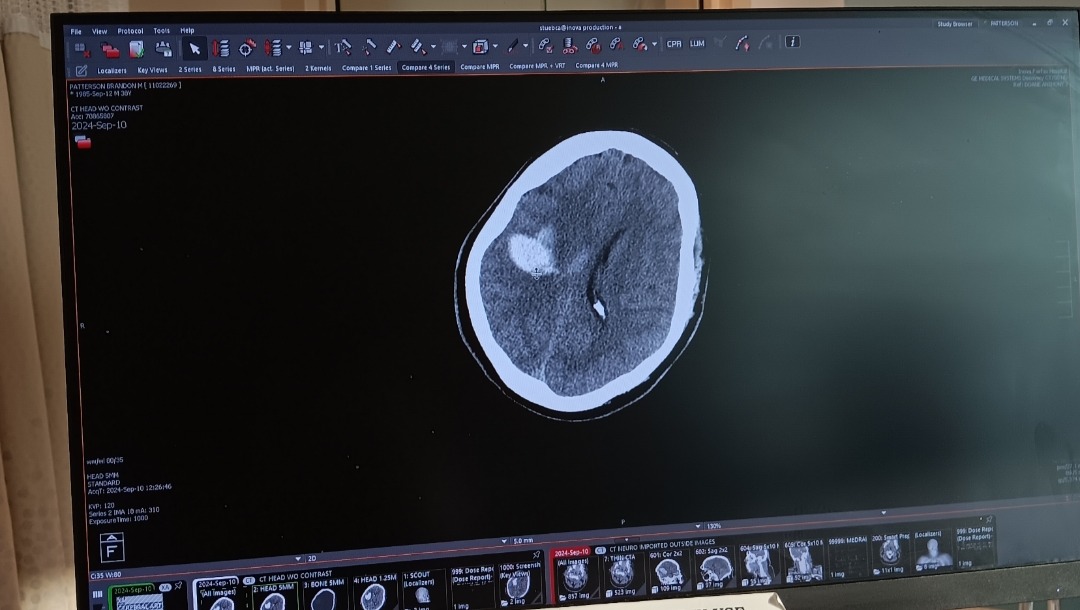

My name is Katie and my husband, Brandon, had a right side brain bleed that led to a stroke. He had to be life-flighted from UVA Hospital to INOVA Fairfax Hospital and was placed in the Neuro ICU, which is where he remains presently. His whole left side is completely paralyzed, he's not able to move, and I know we have a long road to recovery ahead.